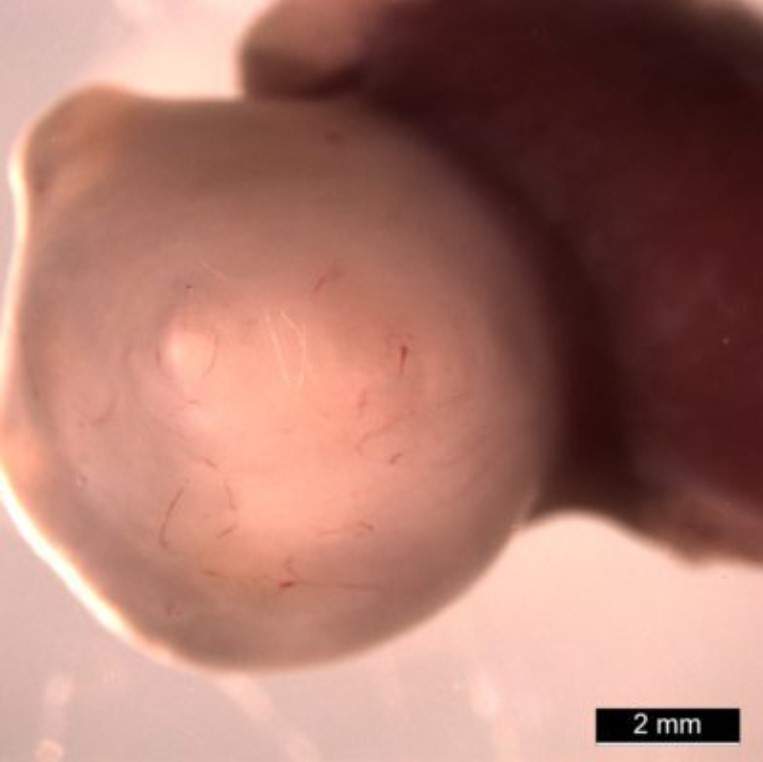

Органоид желудка 10-недельного возраста, который растет внутри мыши

Фото: Медицинский центр детской больницы Цинциннати